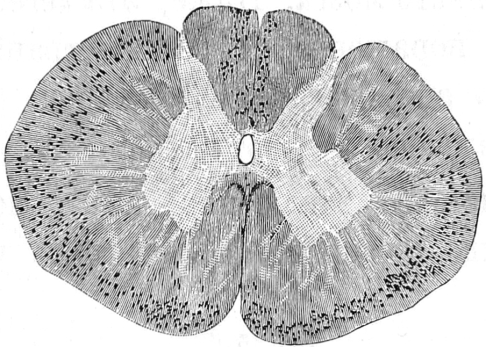

Названные авторы воспользовались съ одной стороны опытомъ Stenson’a а съ другой изслѣдованіями Conheim’a и Litten’a объ ишемическомъ некрозѣ, вполнѣ правильно предполагая, что замѣчаемый при перевязкѣ аорты параличъ заднихъ конечностей зависитъ отъ некроза сѣраго вещества спинного мозга и что при продолжительной перевязкѣ возможно сѣрое вещество совершенно разрушить; такимъ образомъ, пользуясь перевязкой брюшной аорты, они задались цѣлью вылущить,,herausschälen“ сѣрое вещество спинного мозга и, благодаря этому, узнать анатомическое отношеніе его къ окружающимъ частямъ. Для производства зажатія аорты они пользовались способомъ Du Bois-Raymond’a [22]). Зажимали брюшную аорту на 1 часъ. Въ большинствѣ случаевъ авторы наблюдали продолжительный двигательный и чувствительный параличъ задней половины животнаго. Въ спинномъ мозгу животныхъ, жившихъ послѣ перевязки брюшной аорты довольно продолжительное время, авторы нашли очень интересныя измѣненія: сѣрое вещество спинного мозга на всемъ протяженіи сильно съужено, такъ что оно приняло видъ двухъ изогнутыхъ узкихъ полосъ; міэлиновыя волокна сѣраго вещества уже не открываются по методу Weigert’a за исключеніемъ заднихъ роговъ, гдѣ еще остались нѣкоторыя изъ волоконъ; гангліозныя клѣтки исчезли совершенно, между тѣмъ какъ заднія корешки и спинныя гангліи совершенно нормальны.

Въ бѣломъ веществѣ авторы нашли также большія измѣненія: передніе и передне-боковые столбы, за исключеніемъ въ послѣднихъ двухъ узкихъ поясковъ, перерождены; одинъ изъ поясковъ, оставшійся неизмѣненнымъ, соотвѣтствуетъ по- мнѣнію обоихъ авторовъ, по всей вѣроятности, переднимъ пирамиднымъ пучкамъ, второй же соотвѣтствуетъ боковымъ мозжечковымъ пучкамъ человѣка. Такимъ образомъ, согласно изслѣдованію Ehrlich’a и Brieger’a все бѣлое вещество, исключая заднихъ и такъ называемыхъ длинныхъ пучковъ, перерождено.

C. Spronck 25) въ своей работѣ: „Contribution а l'etude experimentale des lesions de la moelle épiniere determinées par l’anemie passagére de cet organe", вполнѣ подтверждаетъ опыты Ehrlich’a и Brieger’a и описываетъ наблюдавшіяся измѣненія въ спинномъ мозгу: нервныя волокна сѣраго вещества, за исключеніемъ заднихъ корешковыхъ волоконъ и центральныхъ волоконъ переднихъ и боковыхъ столбовъ перерождаются, Дейтерсовы отростки гангліозныхъ клѣтокъ переднихъ роговъ отдѣляются отъ послѣднихъ и распадаются на 4-й день. Распадъ мякотныхъ волоконъ обыкновенно сопровождается варикозной гипертрофіей осевыхъ цилиндровъ.